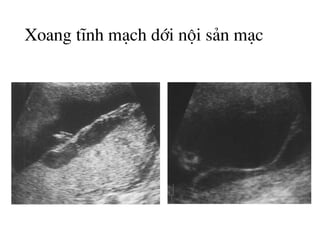

H×nh ¶nh khoang chøa dÞch díi néi s¶n m¹c

Xoang tÜnh m¹ch díi néi s¶n m¹c

H×nh ¶nh khoang chøa dÞch díi néi s¶n

m¹c: Ph©n biÖt víi u b¸nh rau